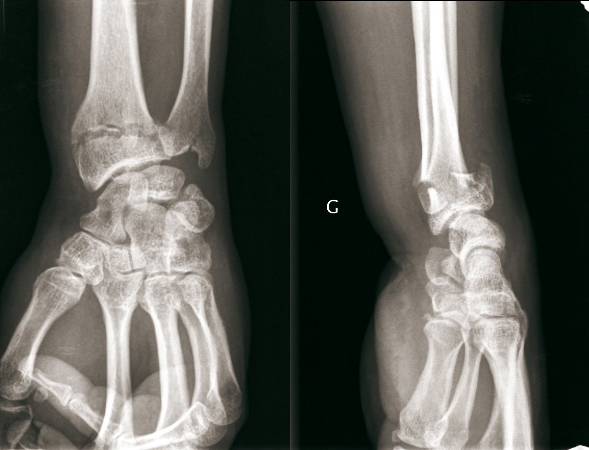

© Henry Coudane, Frédéric Éloy (La Revue du Praticien) Fracture extra-articulaire à déplacement postérieur dit fracture de Gérard Marchand = Pouteau-Colles + fracture styloïde ulnaire. (À gauche) Radio de face.(À droite) Radio de profil.